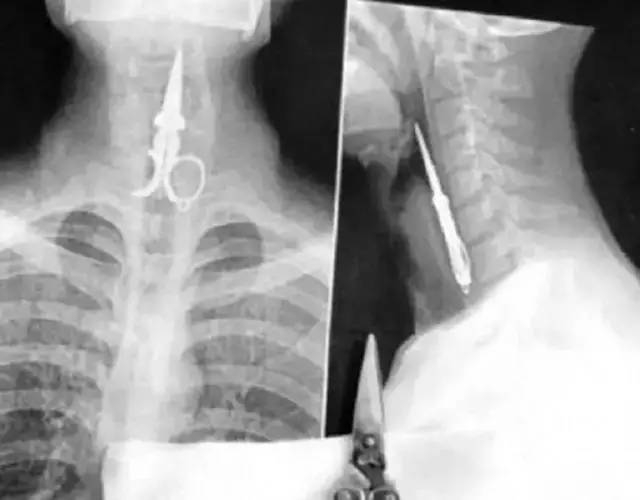

1郑州一名两岁多的男宝小俊,因误吞一个纽扣电池,承受了莫大的痛苦。这是电池卡在食管里的照片!纽扣电池漏出的化学物质,将周围的食管都烧黑了!

用剪刀剔牙,结果剪刀滑入食道……